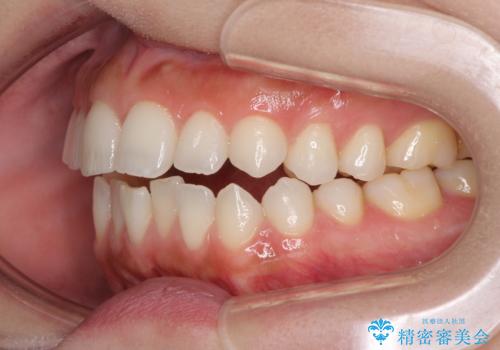

前歯のオープンバイトを治したい インビザラインでの矯正治療

- 前歯の上下スペースによる話しにくさと顎への負担を気にして来院された患者様です。

インビザラインにより上顎の大臼歯を圧下し、上下の前歯の隙間を閉じていくこととしました。

上顎の奥歯を圧下させることで、上下前歯を接触させるように計画しました。

前歯が急に接触するようになり、慣れるまで時間がかかりましたが、前歯でものが咬めるようにもなり、患者様には大変満足していただきました。